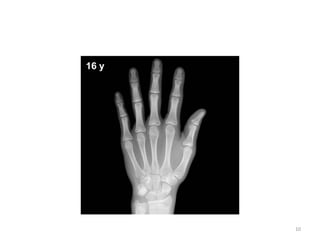

BONE (hand) OSSIFICATION CENTRE APPEARANC E CONJOINT EPIPHYSIS FUSION/U NION First Metacarpal 2-3- 15-17 Proximal phalanges 1.5-2 - 15-18 Metacarpals 2-3 - 15-19 Middle phalanges 2-4 - 15-18 Distal phalanges 2-4 - 15-18 25